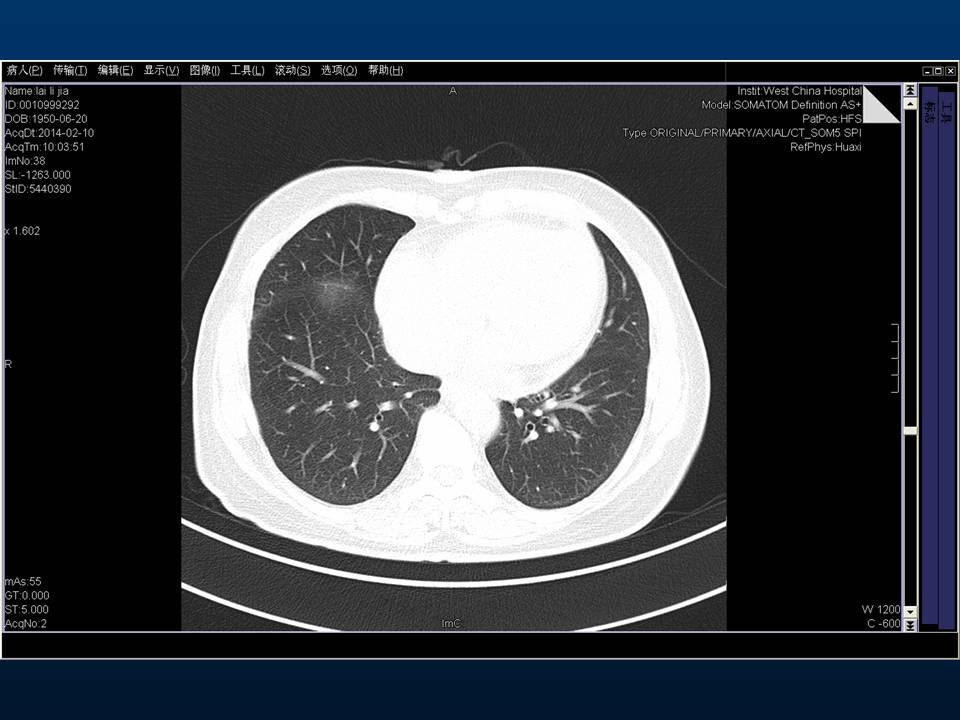

心房颤动(扑动)与“心衰”一例特殊病例报道